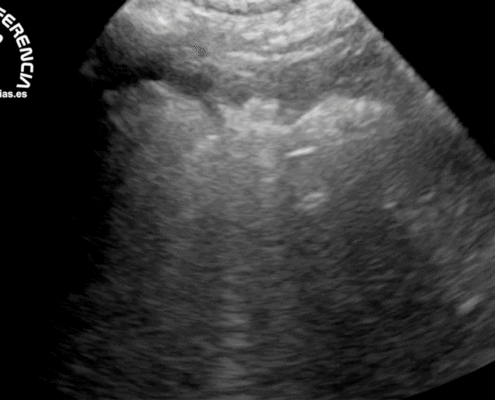

https://www.serveturgencias.es/wp-content/uploads/2020/01/Ecografía-del-shock-cardiogénico-pre.gif7631200José Luis Riveirohttps://www.serveturgencias.es/wp-content/uploads/2019/11/logo-serveturgencias-negro.pngJosé Luis Riveiro2020-01-12 18:58:532020-01-13 09:42:17Ecografía shock cardiogénico Servet UrgenciasEspecialidad imprescindible en nuestro servicio quirúrgico ya que anestesiar, especialmente animales mayores o con patologías graves, requiere una valoración previa del sistema cardiorrespiratorio, para establecer como, cuando y con que métodos se va a garantizar la sedación, la anestesia y la analgesia durante todo el procedimiento quirúrgico